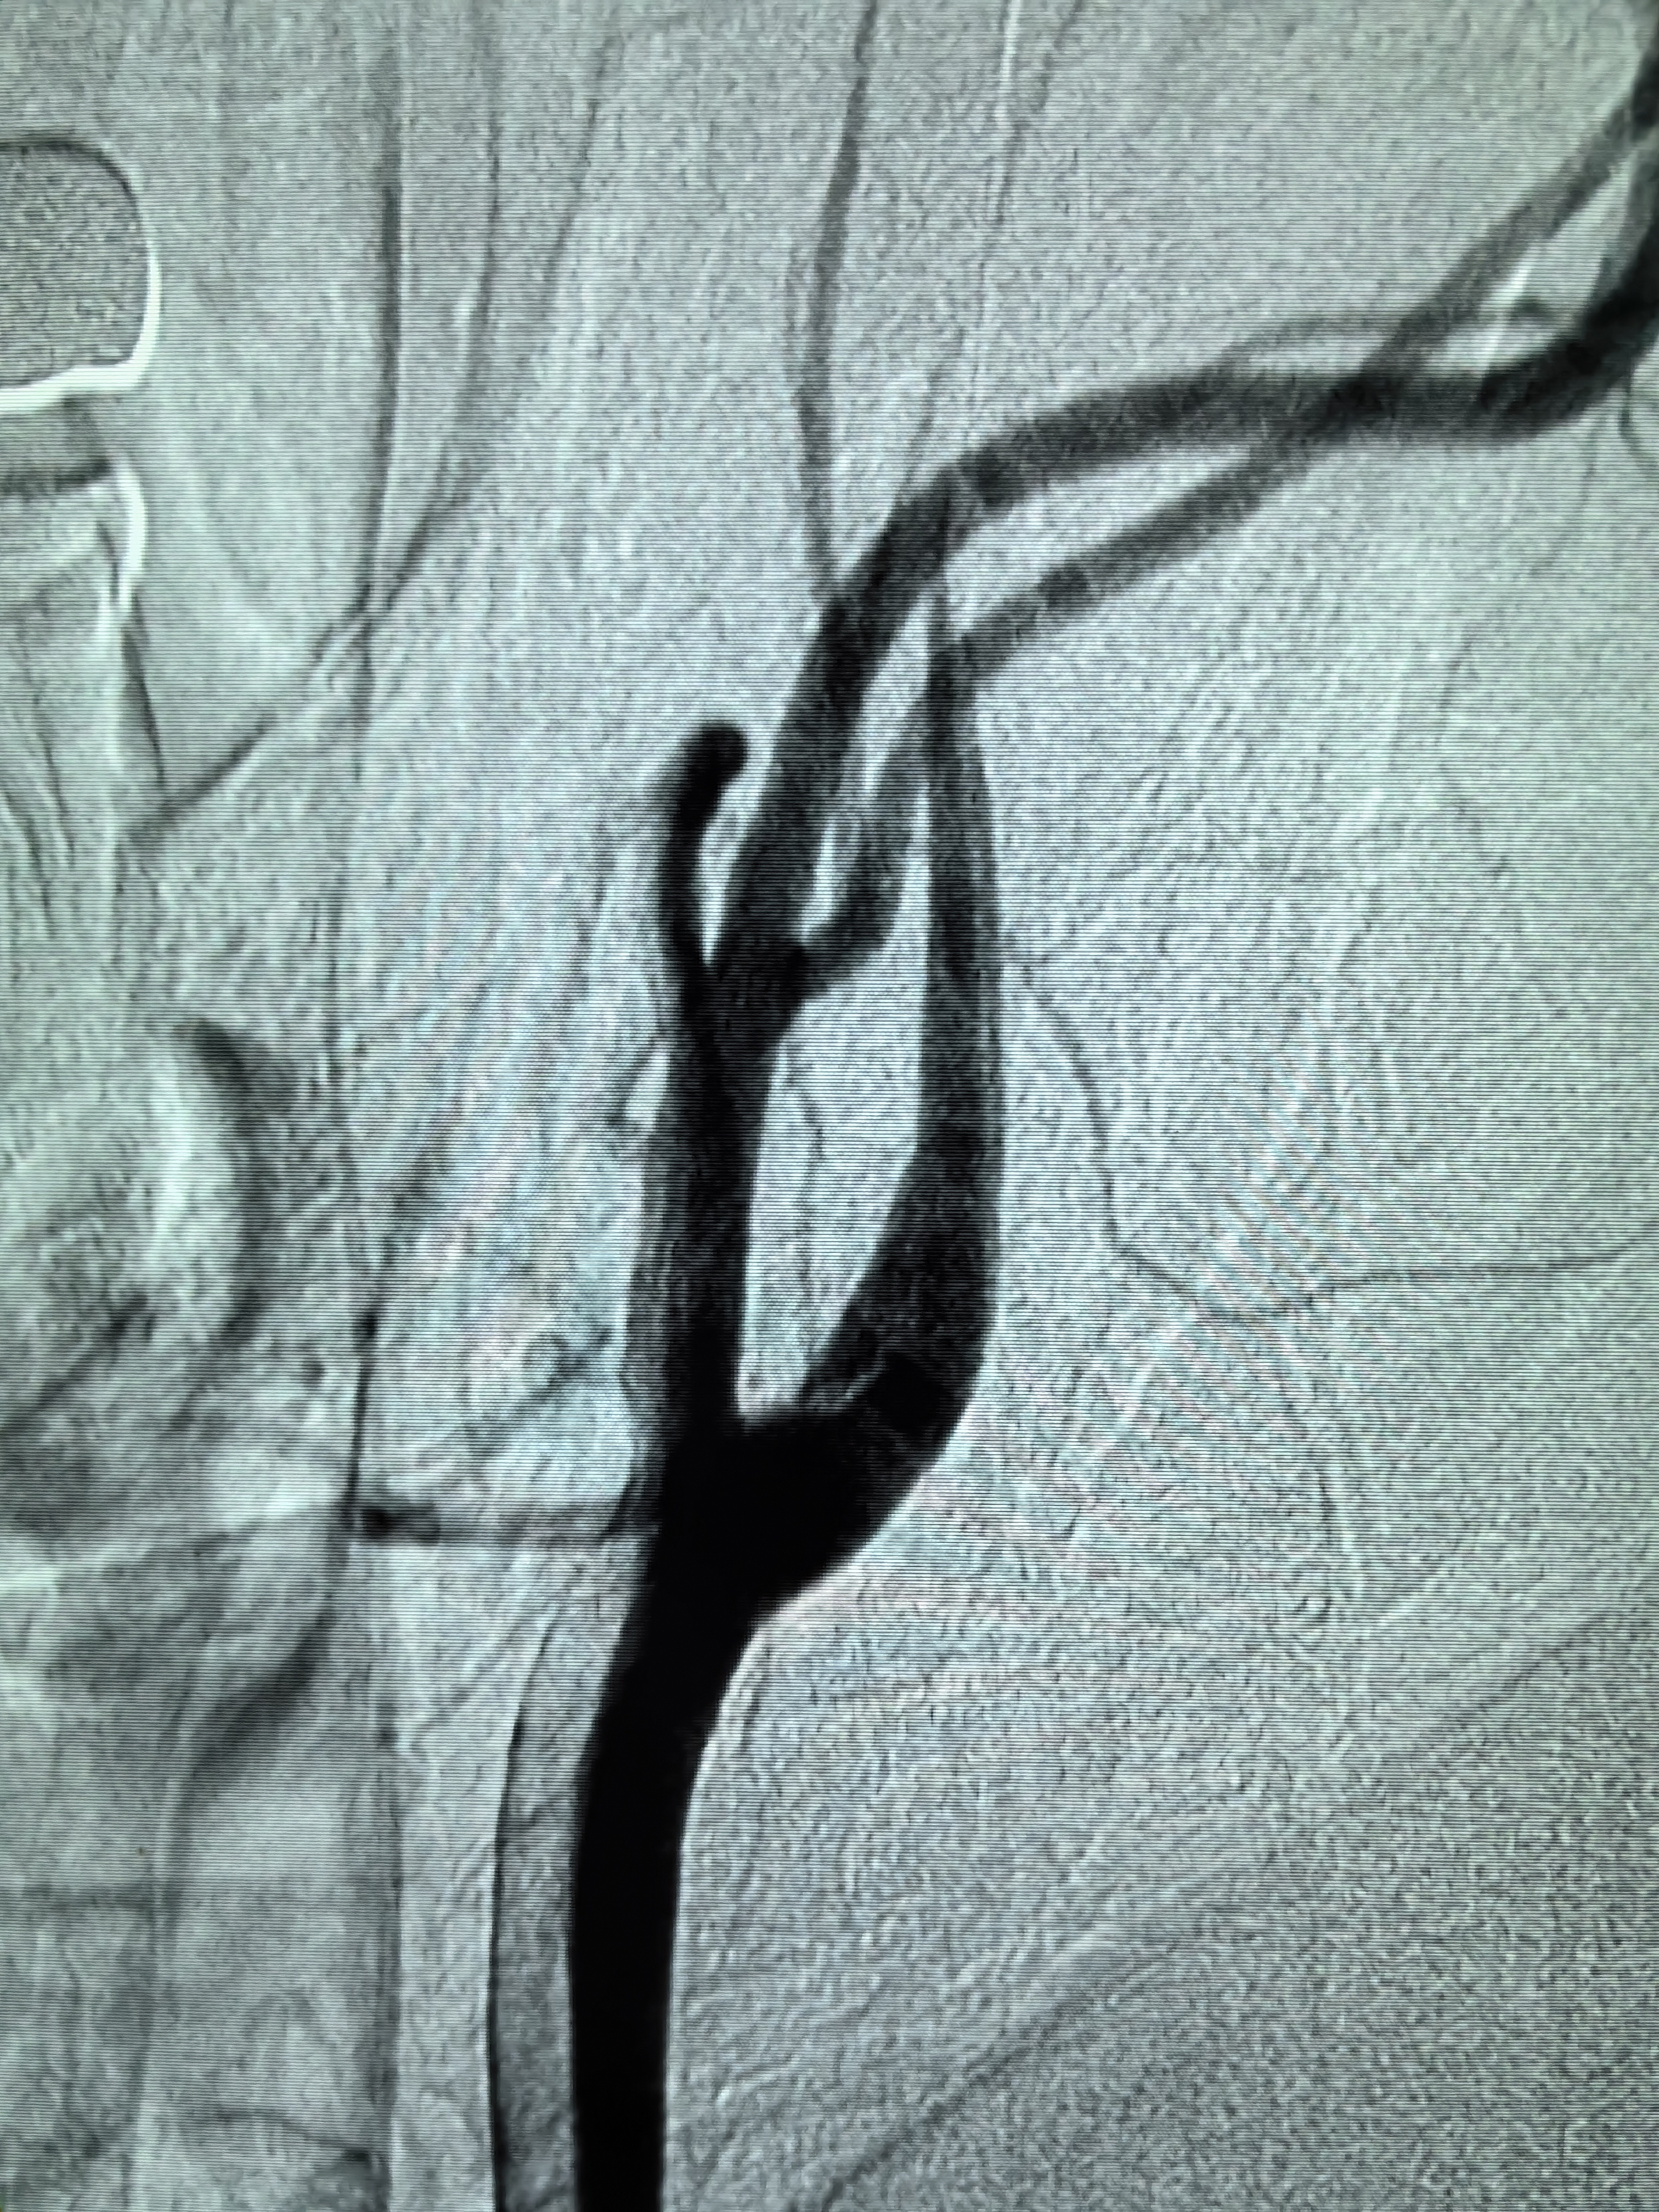

患者术前明确右侧颈内动脉系统栓塞,遂快速建立8F导引导管+CAT6中间导管取栓路径,微导丝携微导管顺利通过病变。